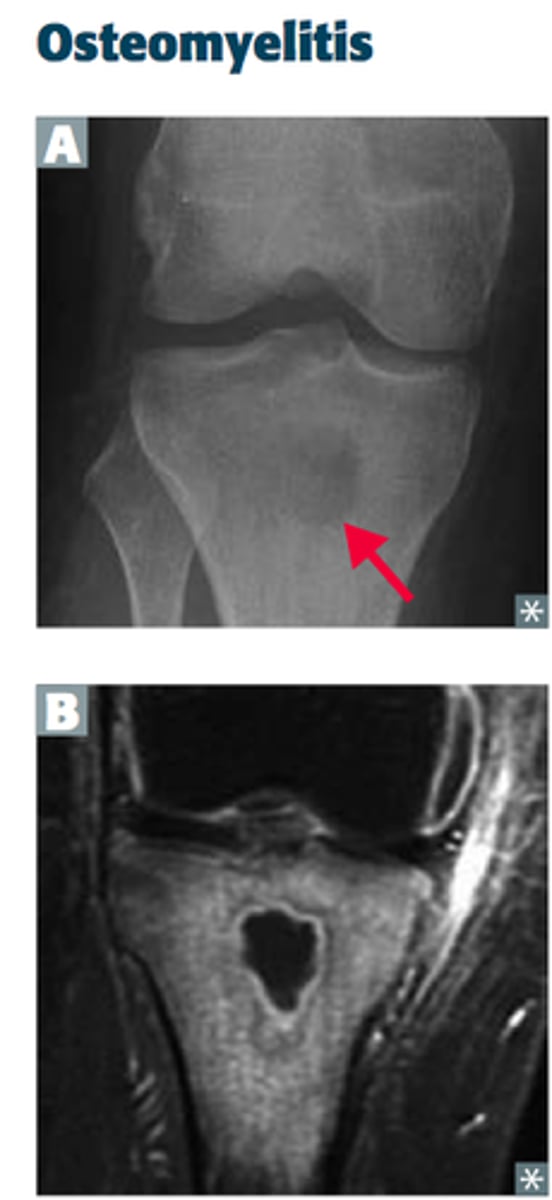

What is osteomyelitis due to?

Hypovascularity

What do you feel during acute osteomyelitis?

Pain

Is there radiograph manifestation during the acute phase of osteomyelitis?

No

Which gender is more affected by osteomyelitis in the mandible?

Men

What indicates osteomyelitis if borders are irregular?

Choose osteomyelitis

What is sequestration in chronic osteomyelitis?

Necrotic bony islands

What develops during chronic osteomyelitis?

Sinus tract